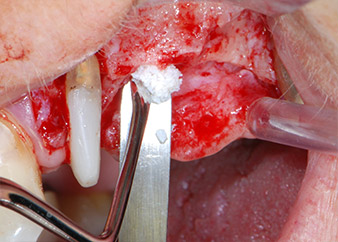

Преди поставянето на имплант, и последвалото потвърждение за непокътната Шнайдерова мембрана (Фиг. 9), вътрешният синус е повдигнат и в двете места на имплантите с помощта на ксеногенен костозаместващ материал (Bio-Oss, Geistlich Biomaterials) (Фиг. 10).

Имплантите (Restore, Keystone Dental, диаметър 3,75 mm, дължина 8.0 mm) са поставени с имплантологичен мотор

(Фиг. 11 и 12).